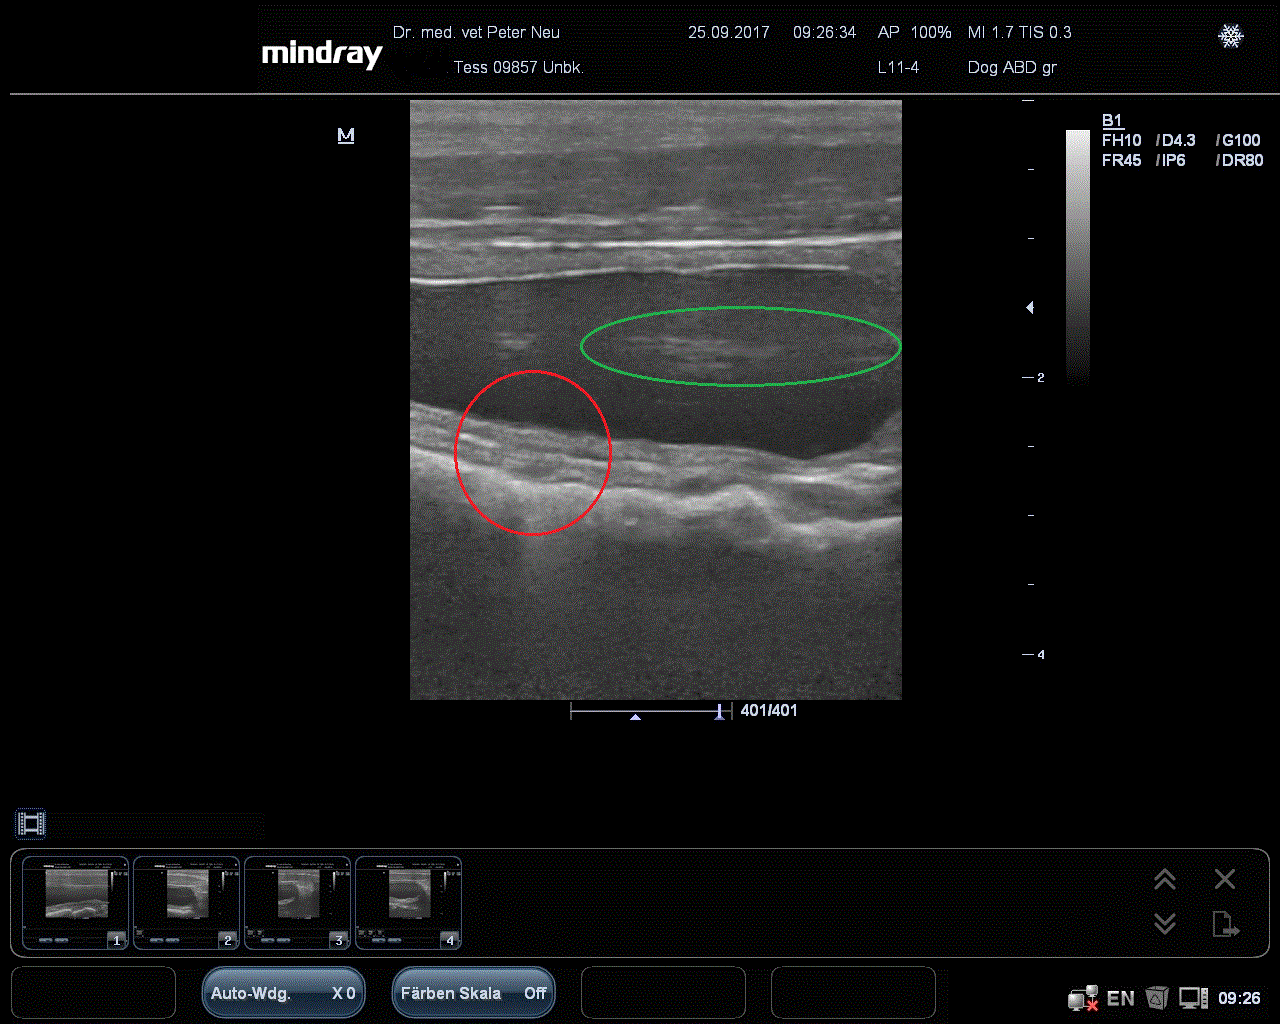

Heute möchte ich Euch mal einen sehr ungewöhnlichen Fall vorstellen. Ein Züchter von Australian Shephard hatte schon seit längerem Probleme mit seiner Hündin “Tess””. Sie litt schon über ein halbes Jahr unter schmerzhaftem Harndrang, man spricht von “Pollakisurie”, und war schon mehrfach auf eine Blasenentzündung mit Antibiotika vorbehandelt worden. Grund genug eine gründliche Untersuchung zu starten. Anfangs denkt man natürlich immer an bakterielle Blasenentzündungen, an Steine oder Blasengries, an Tumore oder auch Erkrankungen der Scheide und Gebärmutter. Also folgte eine Ultraschalluntersuchung, bei der man gleich über eine dünne Kanüle Harn gewinnen konnte. Dieser Urin wird dann mittels Teststreifen, Harn Sedimentation mittels Mikroskop, Spezifisches Gewicht und Bakterienkultur weiter untersucht.….…..und fand erst mal ein Ei. Danach wurde mehr Urin untersucht und konzentriert und man fand den Produzenten. Ein ausgewachsenes Exemplar von Capillaria plica. Somit wurde auch klar, was die länglichen Strukturen (grüne Kreise) waren, nämlich der Wurm selbst, er kann nämlich bis zu 40 cm !!! lang werden.

Unser Team war natürlich überrascht, ein seltener Befund. Und es erklärte Tess Probleme vollständig. Jetzt ging es an die Recherche in Büchern, Google und Fachzeitschriften. Die Nachfrage beim Züchter ergab: Tess war aus einer Zuchtlinie in den USA importiert worden und fraß immer wieder gerne Regenwürmer, BINGO genau den Zwischenwirt von Capillaria plica. Der Literatur nach sollte das Präparat Fenbendzol (Panacur) wirken, also bekamen alle 22 Hunde über 5 Tage Panacur zugefüttert. Der Erfolg war aber gleich Null. Erst eine Umstellung auf das Präparat Levamisol, welches wir Tess als Injektion spritzten un den anderen Hunden als Concurat® Pulver gaben, liess die Symptome endgültig und dauerhaft verschwinden.